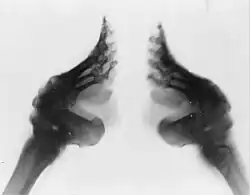

Le bandage commençait à l'âge de cinq ou six ans, parfois plus tôt, et nécessitait environ deux ans pour atteindre la taille jugée idéale de 7,5 centimètres, ou lotus d'or. Après avoir baigné les pieds dans de l'eau chaude ou du sang animal mélangés à des herbes médicinales, les orteils, à l'exception du gros orteil, étaient pliés contre la plante du pied, et la voûte plantaire, courbée, pour réduire sa longueur et donner au pied la forme d'un bouton de lotus. Le pied était ensuite placé dans une chaussure pointue, de plus en plus petite au fil des semaines. Les fractures, volontaires ou accidentelles, étaient fréquentes, en particulier si le bandage commençait à un âge tardif. Les bandes devaient être quotidiennement changées, ainsi que les pieds lavés dans des solutions antiseptiques. Malgré cela, le taux de mortalité des suites de septicémie est estimé à 10 %[2].

Il existait un second procédé, demandant des compressions encore plus fortes, qui entraînait de nombreuses lésions de l'articulation tarsienne et impliquait un déplacement du calcanéum, qui passait sa position naturelle horizontale à une position verticale. Dans les deux cas, des plaques métalliques étaient quelquefois ajoutées sous la plante du pied ainsi bandé[3].

Les orteils, privés d'une grande partie de l'irrigation nécessaire, se nécrosaient rapidement. Les voir tomber n'était pas une mauvaise nouvelle, car cela permettait d'obtenir un pied encore plus petit. De manière générale, la circulation sanguine était largement perturbée et rendait les pieds particulièrement douloureux en hiver. En été, le profond pli qui apparaissait entre le talon et la plante du pied était le siège de multiples infections.